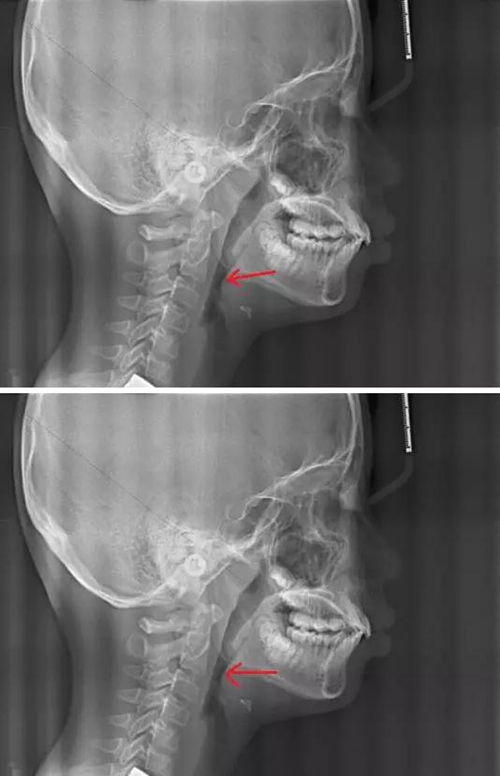

賀老師提到兒童青少年最常見的兩種阻塞呼吸道的問題即腺樣體肥大和扁桃體肥大。首先我們通過頭顱側(cè)位片來了解一下這兩個腺體在x線片上的位置。

以下兩張標(biāo)注的是肥大的腺樣體及其位置

1.jpg